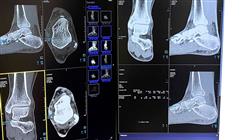

Uma das patologias mais comuns tratadas em consultas de traumatologia e ortopedia é o hálux, especialmente o hálux valgo. O uso de calçados inadequados, cada vez mais comuns no mundo ocidental, tem aumentado o número de pacientes com esses problemas. No entanto, os avanços técnicos permitiram a correção cirúrgica por meio de diferentes técnicas, dependendo da gravidade do caso.

Para isso, este programa conta com uma equipe de professores composta por especialistas em Traumatologia e Ortopedia, que fornecem as informações mais avançadas e abrangentes por meio de um conteúdo teórico-prático. Desta forma, o profissional poderá se aprofundar na deformidade do hálux valgo, também conhecido como joanete, no problema do hálux rígido ou artropatia da primeira articulação metatarsofalângica, na deformidade do hálux varo e nos problemas do sistema ou complexo de sesamoide.

Na TECH Global University, sabemos que seu tempo é valioso e que você precisa de uma opção flexível para continuar seu desenvolvimento profissional. Por isso, nosso curso é oferecido na modalidade online, permitindo que você acesse os conteúdos de qualquer lugar e no horário que melhor se adapte às suas necessidades. A capacitação online oferece a liberdade de aprender no seu próprio ritmo, sem abrir mão da qualidade educacional. Ao se inscrever em nosso Curso Universitário em Cirurgia do Antepé, você se beneficiará da experiência de nossos profissionais renomados na área de podologia e cirurgia podológica. Ao longo do programa, você adquirirá conhecimentos atualizados sobre as técnicas cirúrgicas mais avançadas para tratar condições como hallux valgus, dedo em martelo e outras patologias que afetam o primeiro raio do pé. Além disso, aprenderá a realizar avaliações clínicas precisas, interpretar exames radiológicos e planejar de forma personalizada o tratamento cirúrgico mais adequado para cada paciente. Nossa abordagem prática permitirá que você aplique os conhecimentos adquiridos por meio de casos clínicos e simulações virtuais, proporcionando a confiança necessária para realizar intervenções bem-sucedidas em sua prática profissional. Destaque-se em sua área e expanda suas habilidades na cirurgia do antepé com o respaldo acadêmico da TECH Global University. Inscreva-se em nosso Curso Universitário em Cirurgia do Antepé: Patologias do Primeiro Raio e torne-se um profissional altamente capacitado no tratamento cirúrgico das condições do primeiro raio do pé. Seu crescimento profissional começa aqui!